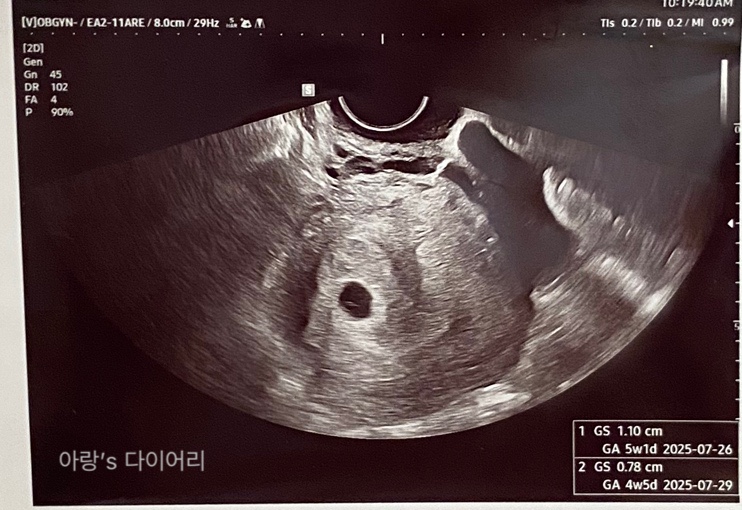

둘째일기 세번째 산부인과 방문 첫 초음파 아기집본날

배란이 평소보다 4일정도 늦게되어 배란 20일차 였지만 마지막 생리일 기준으로는 5주 3일이던 날 임신이 ...